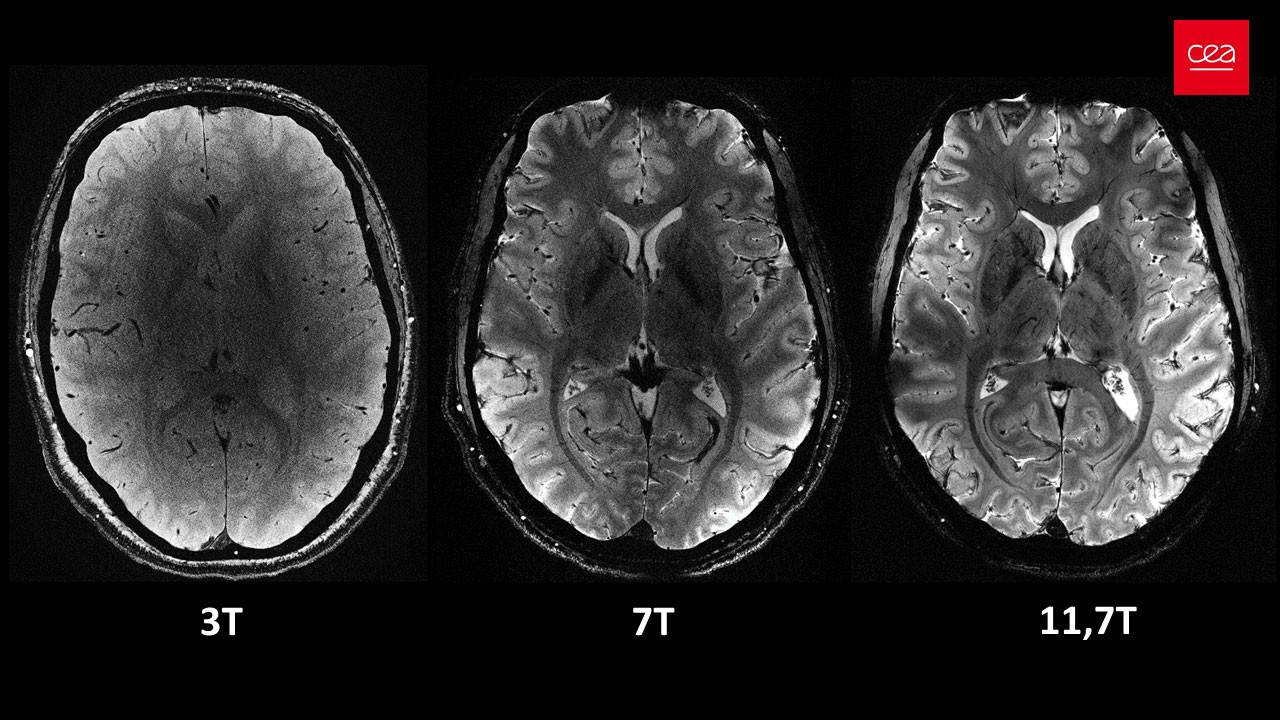

A 3 T, aimant d’IRM couramment utilisé dans les centres hospitaliers, et à 7 T, (seules 3 machines en France et une centaine dans le monde), la précision et la netteté sont moindres. A 3 T, un nuage « granuleux » empêche de délimiter clairement les structures anatomiques du cerveau. A 7 T, lorsque l’on zoome, le niveau de détail à cette résolution est amoindri. A 11,7 teslas, l’IRM Iseult, le seul actuellement en fonctionnement au monde à cette intensité, fournit un réservoir de signaux et de contrastes entre les tissus biologiques qui permet une exploration plus fine du cerveau humain.

Seulement quatre minutes ont suffi pour acquérir certaines des plus belles images anatomiques de cerveau. L'appareil Iseult installé au CEA utilise l’imagerie par résonnance magnétique. Il est le plus puissant au monde avec son champ magnétique de 11,7 teslas. La résolution des images est impressionnante de par son temps d’acquisition si court : 0,2 mm dans le plan et 1 mm en profondeur, représentant un volume équivalent à quelques milliers de neurones seulement.